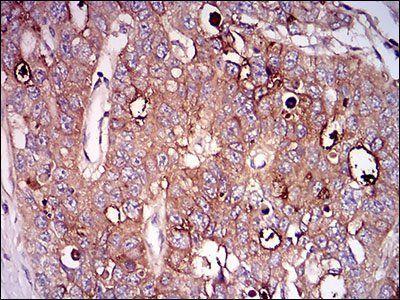

IHC staining of FFPE human pancreatic carcinoma with CD73 antibody (clone NT5E/2545). HIER: boil tissue sections in pH9 10mM Tris with 1mM EDTA for 10-20 min and allow to cool before testing.

IHC staining of FFPE human colon carcinoma with CD73 antibody (clone NT5E/2545). HIER: boil tissue sections in pH9 10mM Tris with 1mM EDTA for 10-20 min and allow to cool before testing.